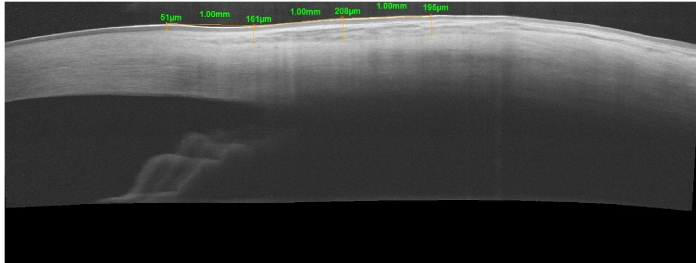

Methods: In this cross-sectional study, patients with pseudoexfoliation and an age-matched control group underwent measurement of bulbar conjunctival thickness in the superior and temporal quadrants, 1, 2, and 3 mm posterior to the limbus using anterior segment OCT.

Abstract Image